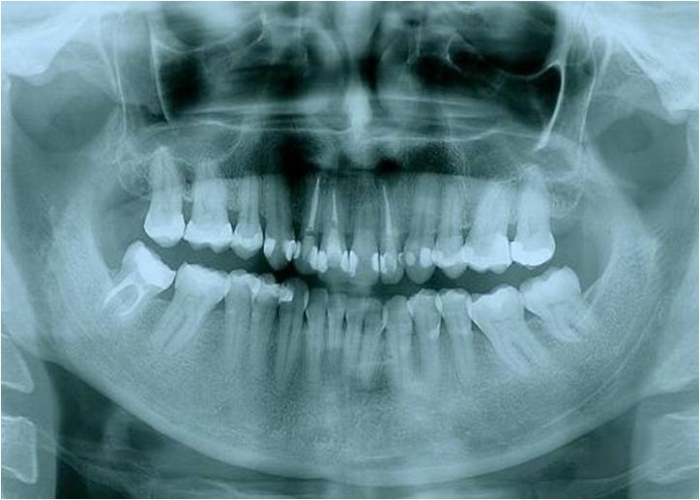

Raio x inicial com presença de lesão periapical no incisivo lateral superior esquerdo - Clínica Cliniface

Raio x inicial com presença de lesão periapical no incisivo lateral superior esquerdo